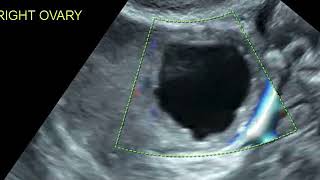

How to measure cervical length on ultrasound??